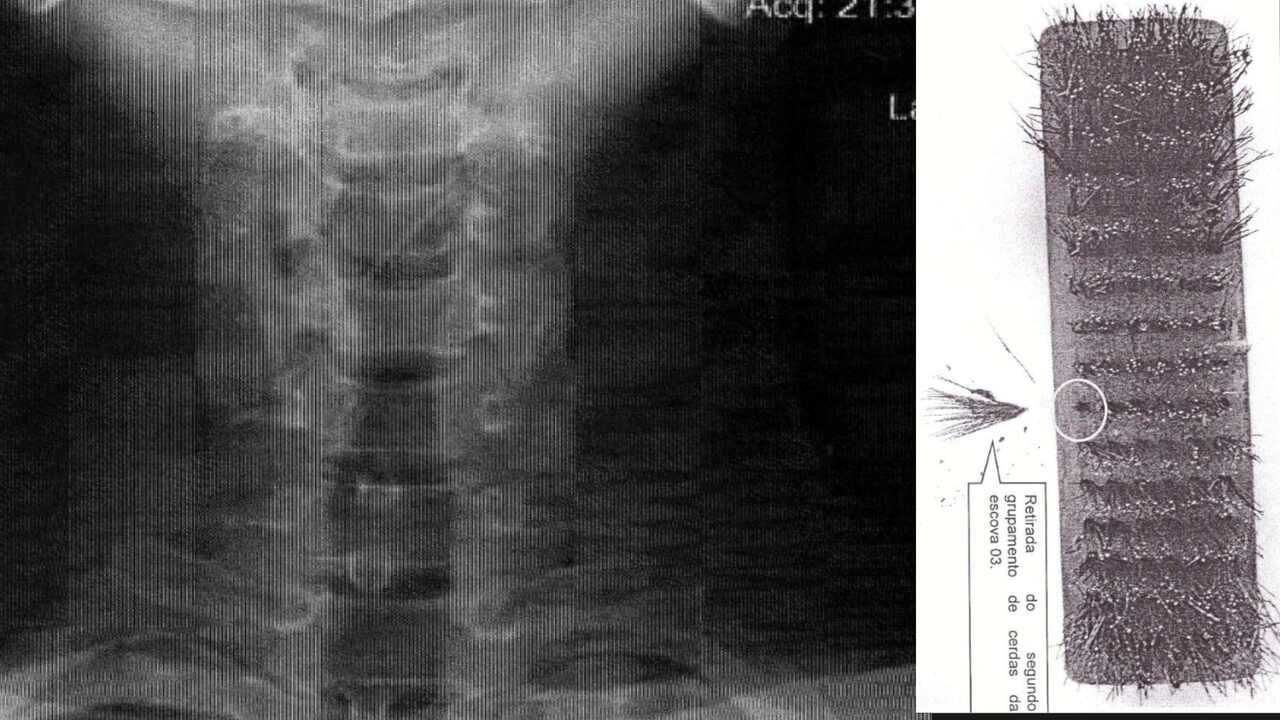

Ainda assim, sentiu que algo estava preso na garganta e procurou atendimento médico na Santa Casa. Um raio-x mostrou um corpo estranho na laringe da vítima e, após retirada, foi confirmado ser uma espécie de arame. No decorrer do inquérito policial, foi descoberto que o objeto era a cerda de uma escova de aço usada para limpar a chapa no Habib’s.